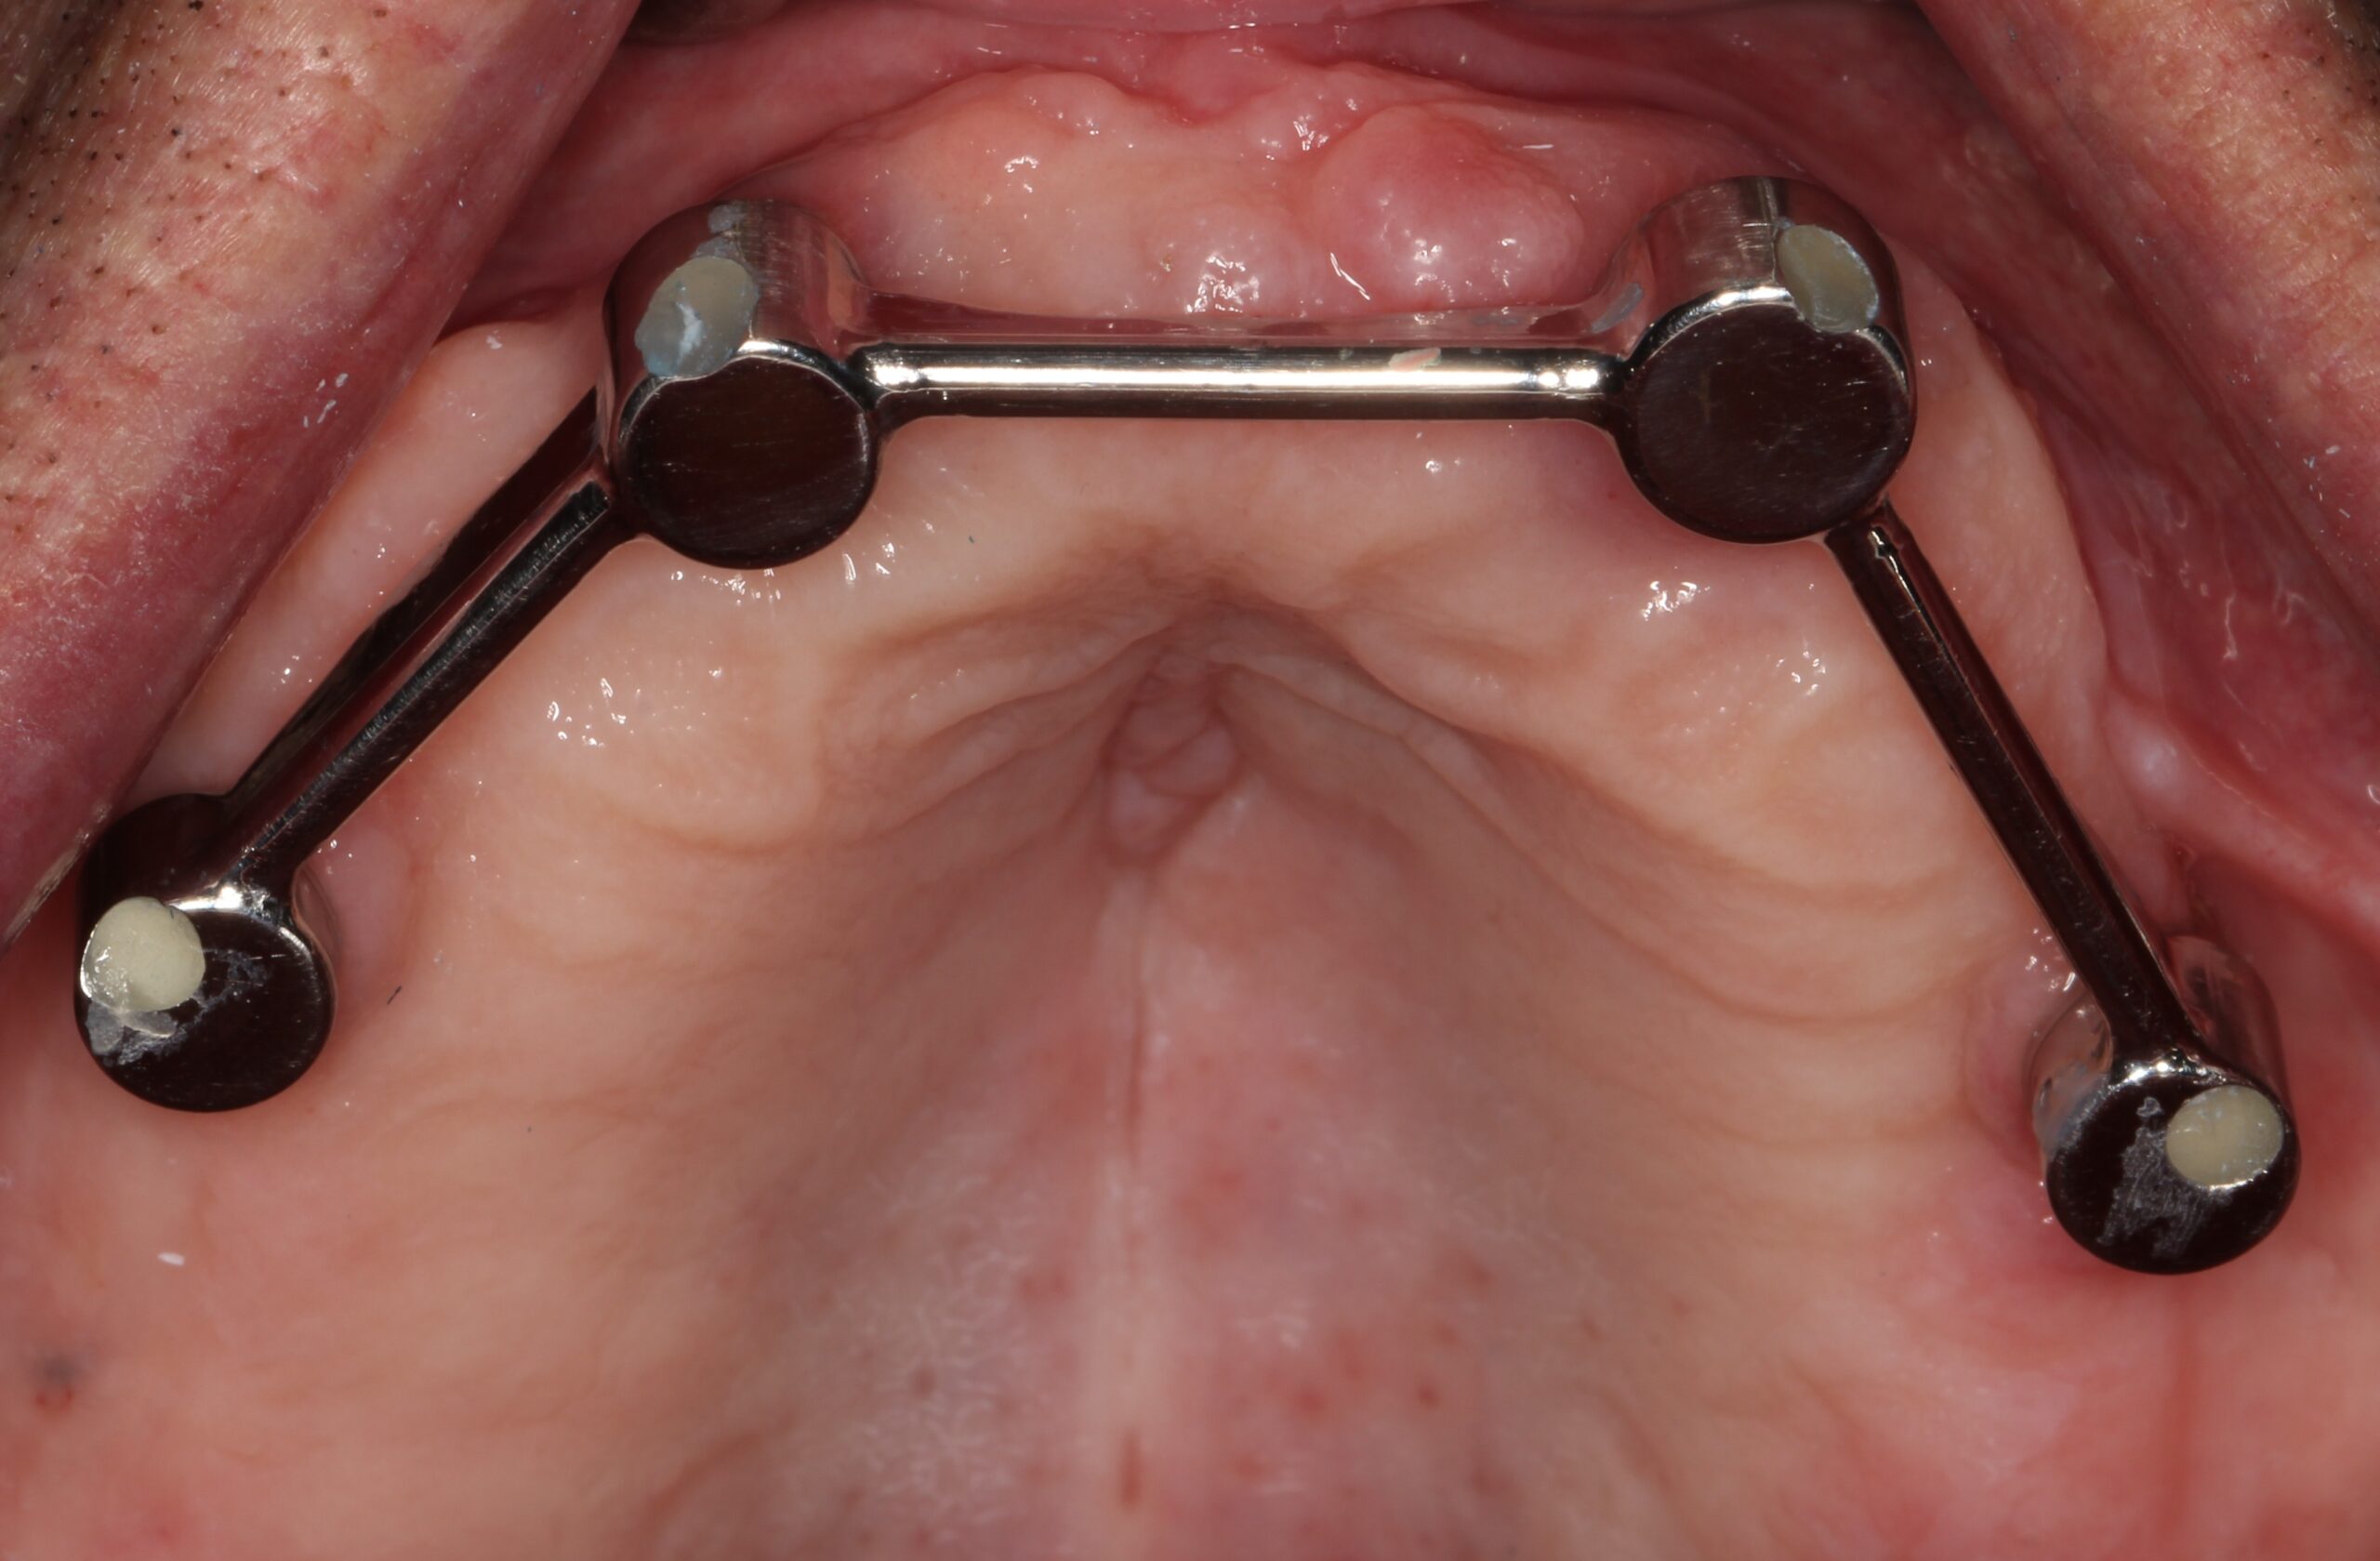

- Bar-retained dentures — A thin metal bar that follows the curve of your jaw is attached to the implants that have been placed in your jawbone. Clips or other types of attachments are fitted to the bar, the denture or both. The denture fits over the bar and is securely clipped into place by the attachment

Lower Jaw Bar Implant Overdentures